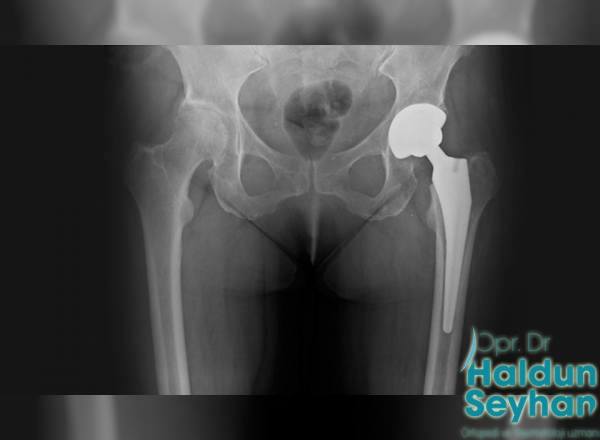

Kalça protezi, çeşitli sebeplerle bozulma yaşanmış eklem yüzeyine yerleştirilen, kobalt-krom veya titanyumdan oluşan ana parçalar olmak üzere, bu parçaların eklemleştiği yerde polietilen, metal ya da seramik parçalardan oluşmaktadır. …

Kalça protezi ameliyatı farklı şekillerde yapılabilir. Yaşı ilerleyen hastalarda kemik kalitesi düşük olabilir. Bu hastalara protez kemik çimentosu adı verilen bir dolgu maddesi yardımıyla işlem yapılabilir. …

Total kalça artroplastisi, eklemin yumuşak hareketini sağlamak için metal, seramik ve polietilenden yapılmış yıpranmış eklem yüzeylerini özel olarak tasarlanmış parçalarla kaplayarak yapay bir eklem oluşturmak için tasarlanmıştır. …